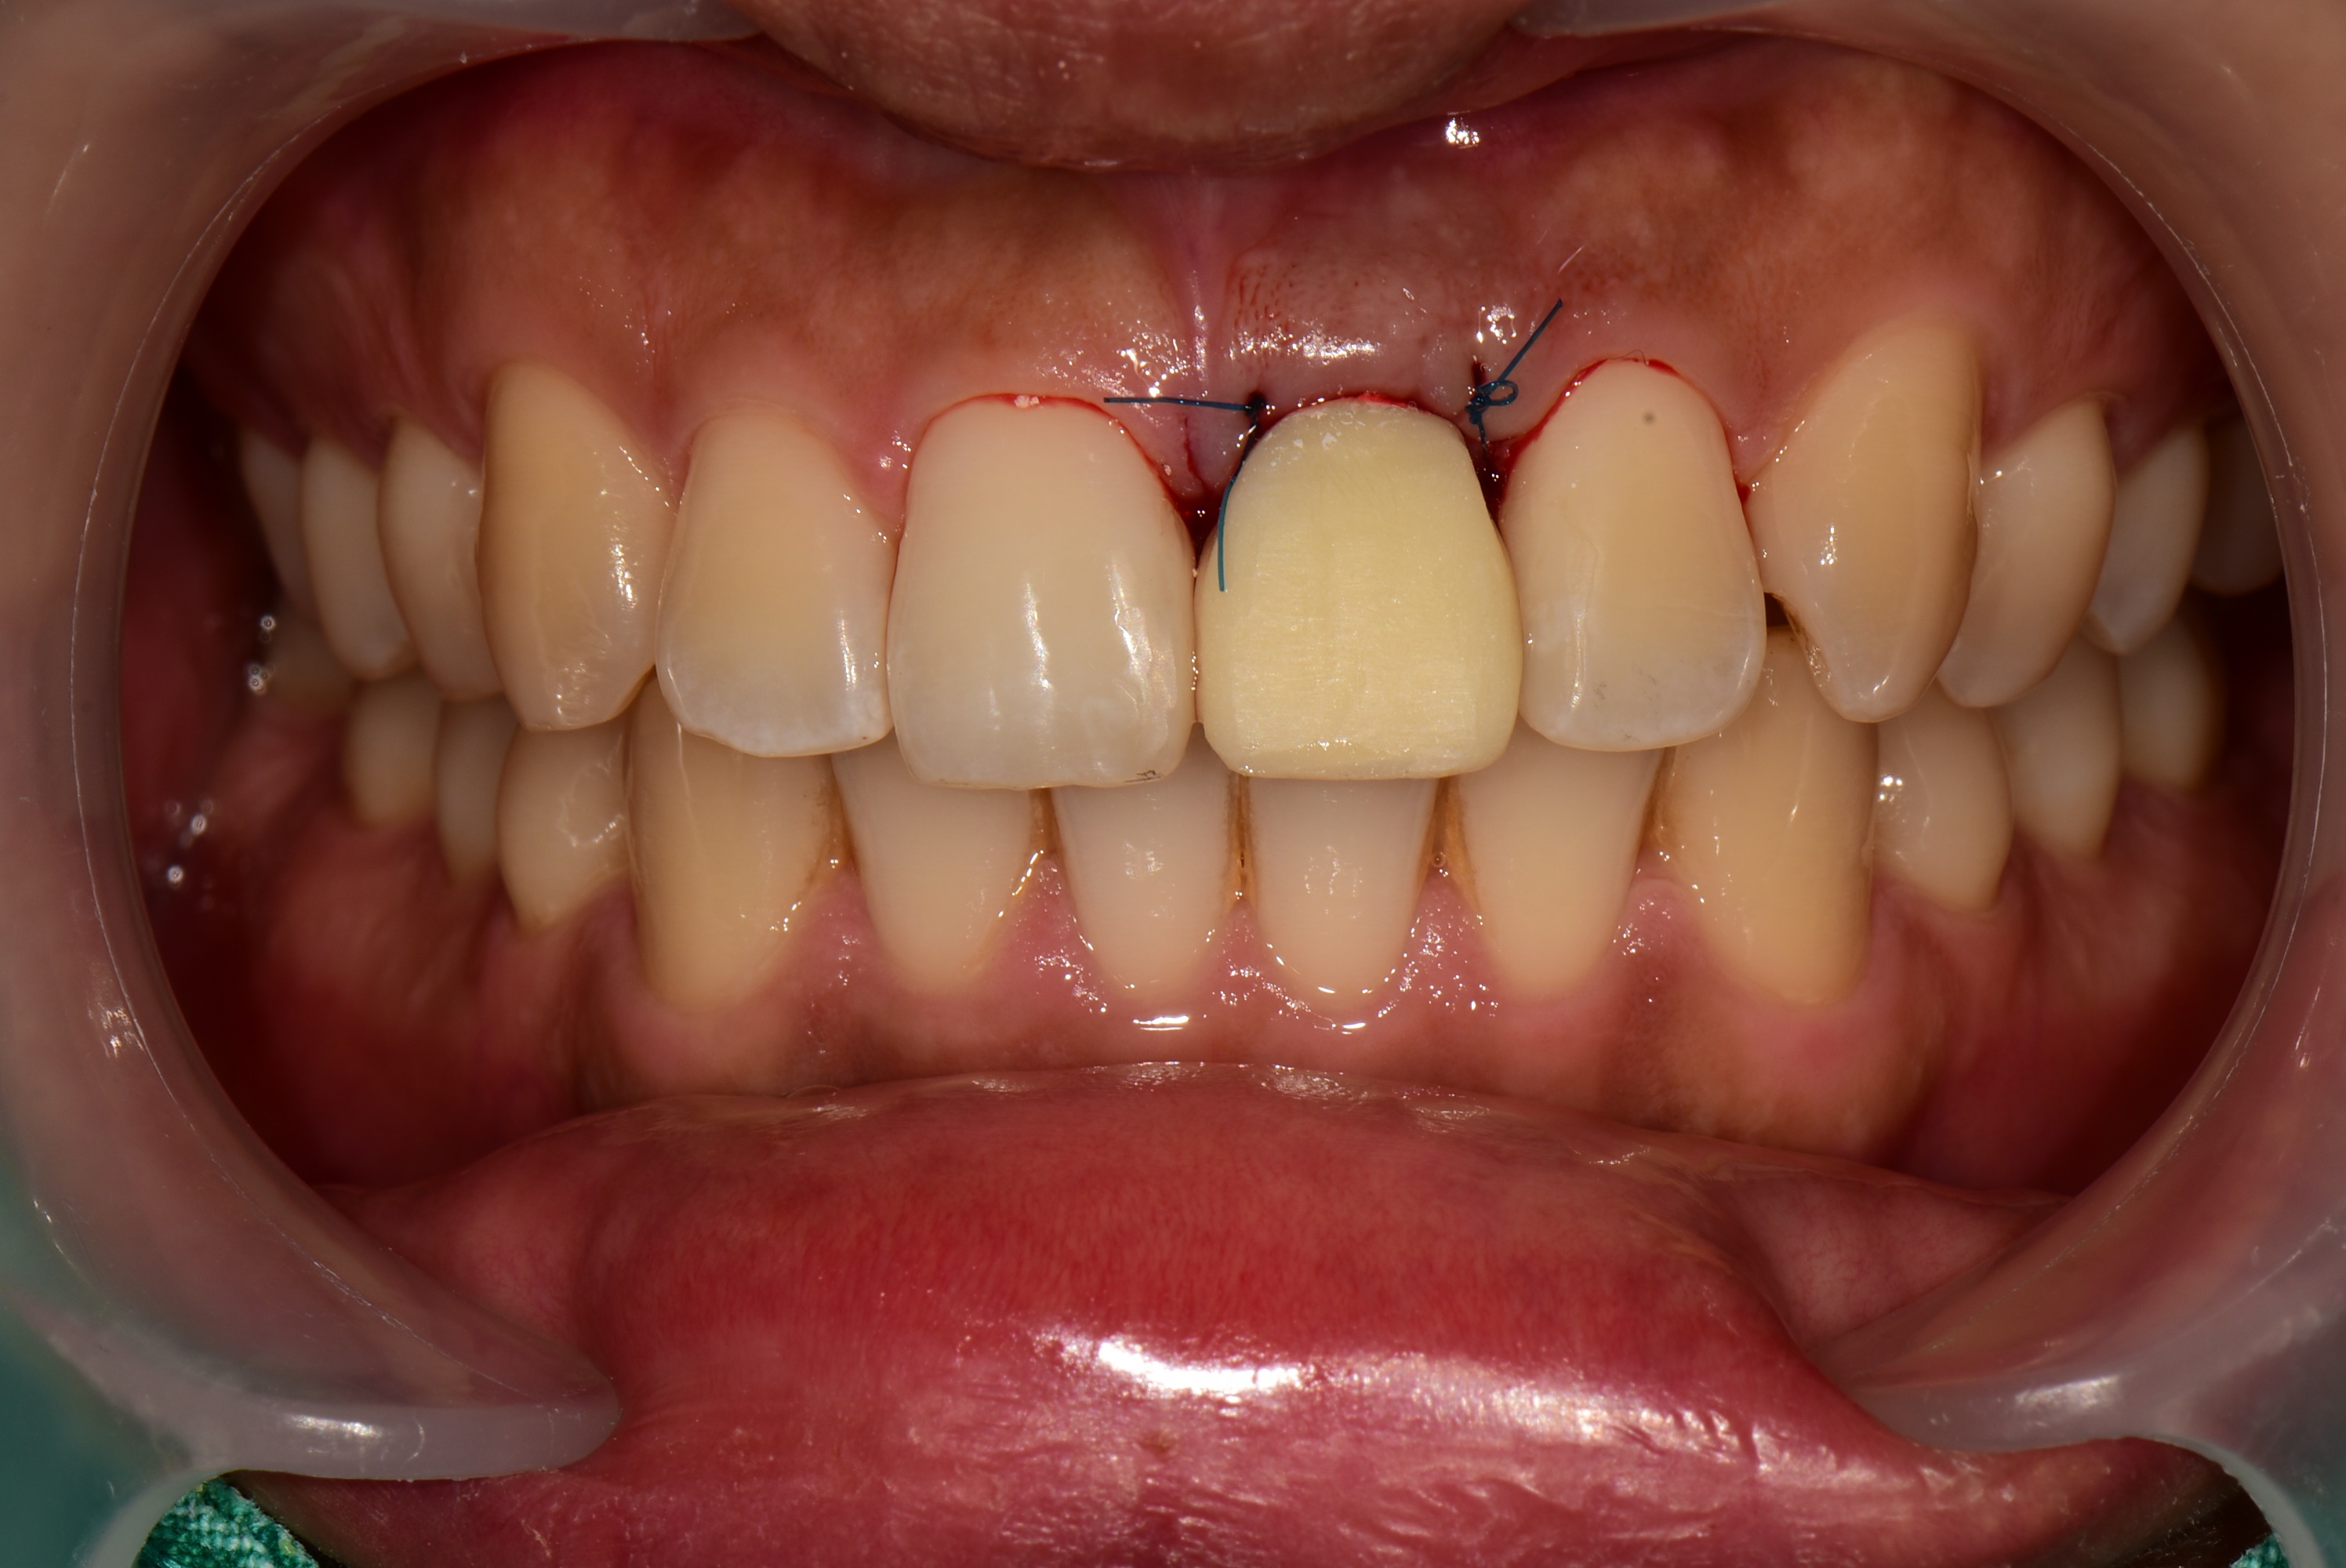

수술 후 임시치아를 먼저 해드렸습니다. 당일 제작한 임시치아는 색상이나 형태가 심미적이지는 않습니다.

3개월 후 앞니 임플란트 최종 보철을 마무리 한 사진입니다.